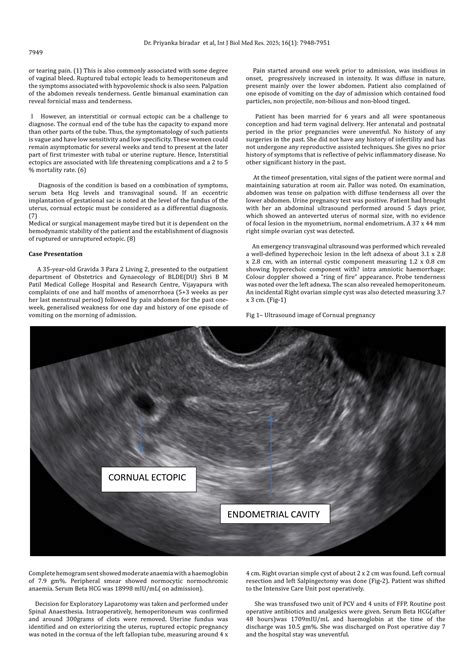

A Cornual Interstitial Pregnancy is a rare and potentially life-threatening form of ectopic pregnancy that requires urgent medical attention. Unlike a typical ectopic pregnancy, where the fertilized egg implants in the fallopian tube, an interstitial pregnancy occurs when the embryo implants in the proximal portion of the fallopian tube, located within the muscular wall of the uterus (the cornua). Because this area is highly vascularized and located near the major uterine vessels, these pregnancies carry a significantly higher risk of massive, life-threatening hemorrhage if they rupture compared to other forms of ectopic gestation.

To grasp the gravity of a Cornual Interstitial Pregnancy, it is helpful to understand the unique anatomy of the area. The interstitial segment is the narrowest part of the fallopian tube, traversing the uterine wall. When an embryo implants here, the rapidly growing placenta can invade the surrounding uterine musculature and nearby blood vessels, leading to dramatic internal bleeding as the pregnancy advances.

Diagnosis usually requires a combination of transvaginal ultrasound and serum beta-hCG (human chorionic gonadotropin) monitoring. Radiologists look for specific markers, such as the "interstitial line sign," which helps differentiate this condition from a normal pregnancy or a standard tubal ectopic pregnancy.

Transvaginal Ultrasound The primary tool for locating the gestation sac relative to the uterine cavity.

Interstitial Line Sign A specialized sonographic finding that points specifically to the interstitial segment.